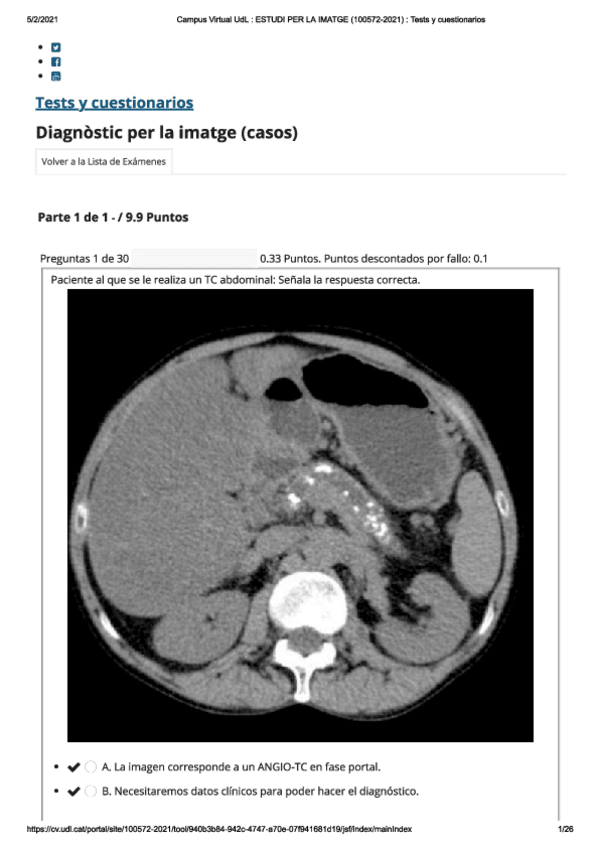

Exámenes - rayos-imagenes.pdf

26 páginas